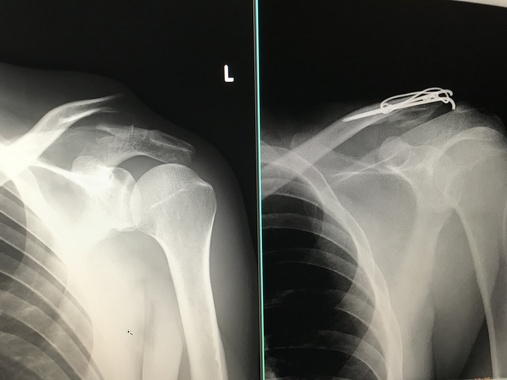

なかなか、、スケルトンな写真を、、、

ありがとうです(笑)

ポッキーって感じでいってますやん。。。

いたそぉ。。。